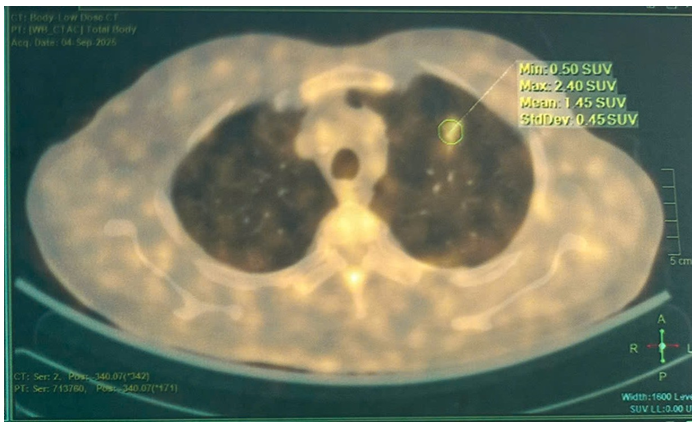

PET/CT:

Hình 4: Hình ảnh vài đám tổn thương dạng kính mờ bờ tua gai ở thùy trên phổi trái, lớn nhất kích thước 17x17mm, tăng nhẹ hấp thu FDG (SUVmax: 2.4) – Theo dõi do viêm.